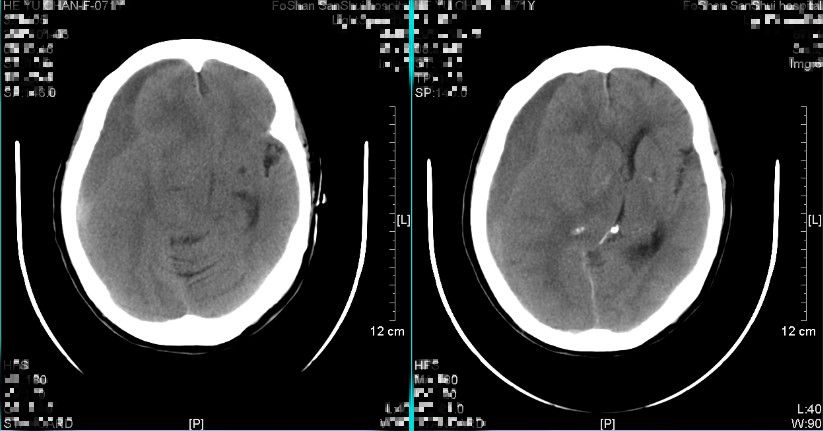

图10. 术后9天复查头颅CT提示亚急性硬膜下血肿基本吸收。(2019-01-12 16:17:43)

经治疗后,患者神志清,头痛等症状缓解,无遗留神经系统缺损体征,复查头颅CT提示亚急性硬膜下血肿基本吸收,病情稳定,于2019年1月14日出院。

2019年1月29日门诊复查头颅CT(图11、图12)如下:提示亚急性硬膜下血肿已吸收,未见新发血肿形成。

图11

图12